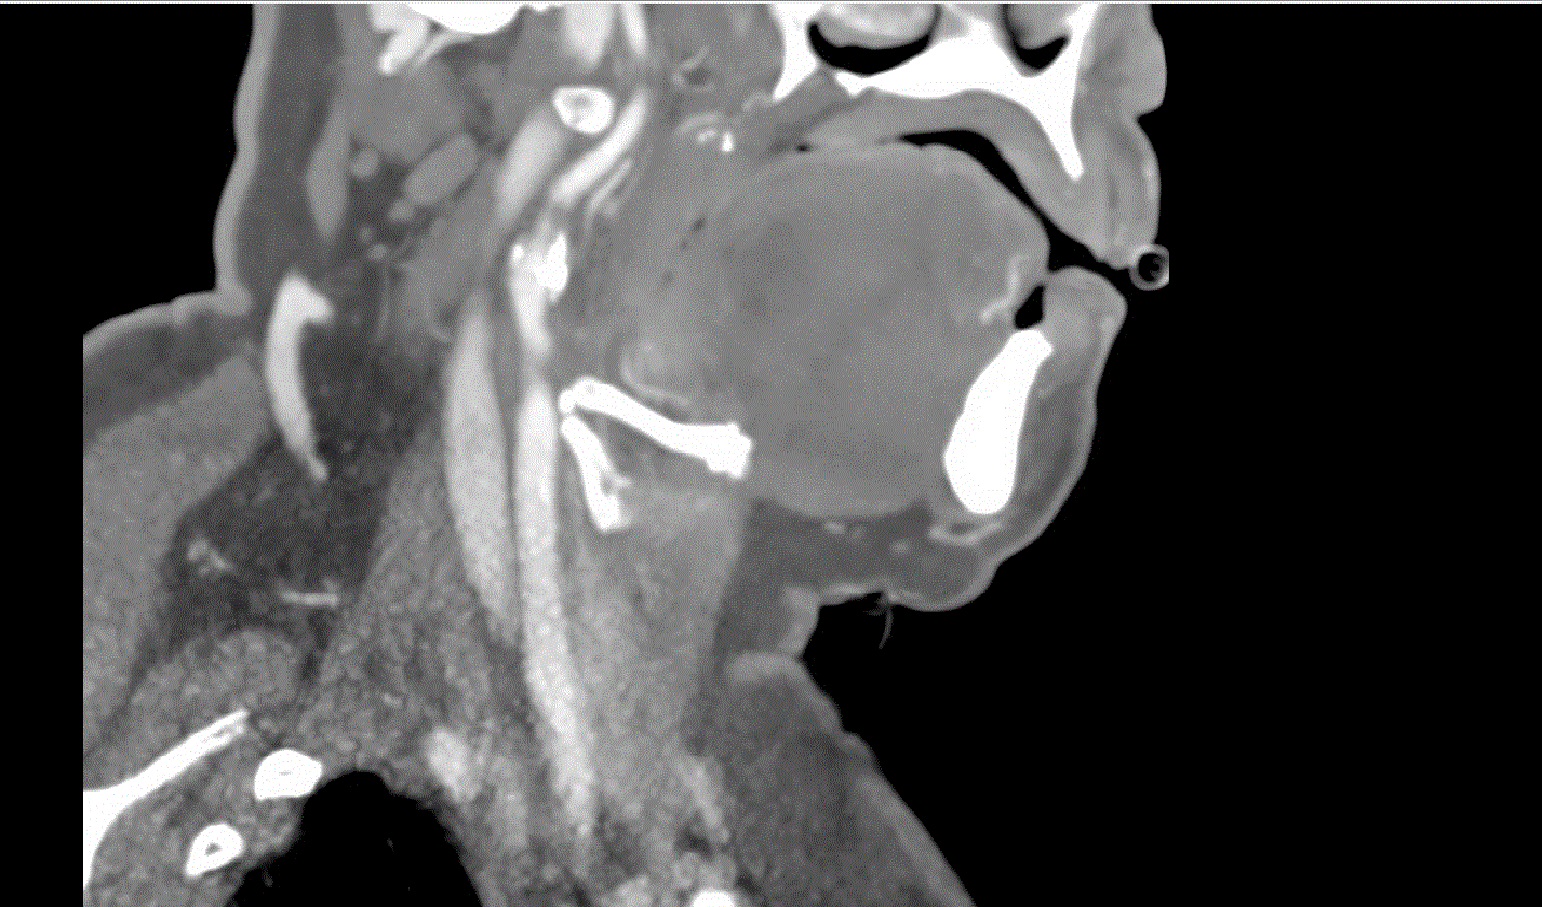

Right total hip arthroplasty was completed successfully. Post operatively she developed left sided weakness. She was hypotensive and received IV fluids. Blood pressure was unable to be obtained in the right arm but left arm BP was 161/91mmHg. CTA of the head and neck showed critical stenosis of the right internal carotid artery; her right subclavian artery was also stenosed. She received aspirin 325mg. Permissive hypertension was initiated. MRI of the brain noted diffusion restriction throughout the right cerebral hemisphere suggestive of a watershed infarct. She underwent carotid endartectomy on post-operative day four.

Hospital medicine was consulted for management of hypertension. She was 1.53m tall, weight 68.5kg, BMI 29kg/m2, with broad shoulders. She had an ejection systolic murmur 3/6 loudest in right upper sternal border with radiation to the carotids; right radial pulse was reduced. She had a left hemiparesis. Gynecological history revealed irregular menses and no pregnancies. Echocardiogram revealed a bicuspid aortic valve with mild stenosis, mild aortic root dilation.